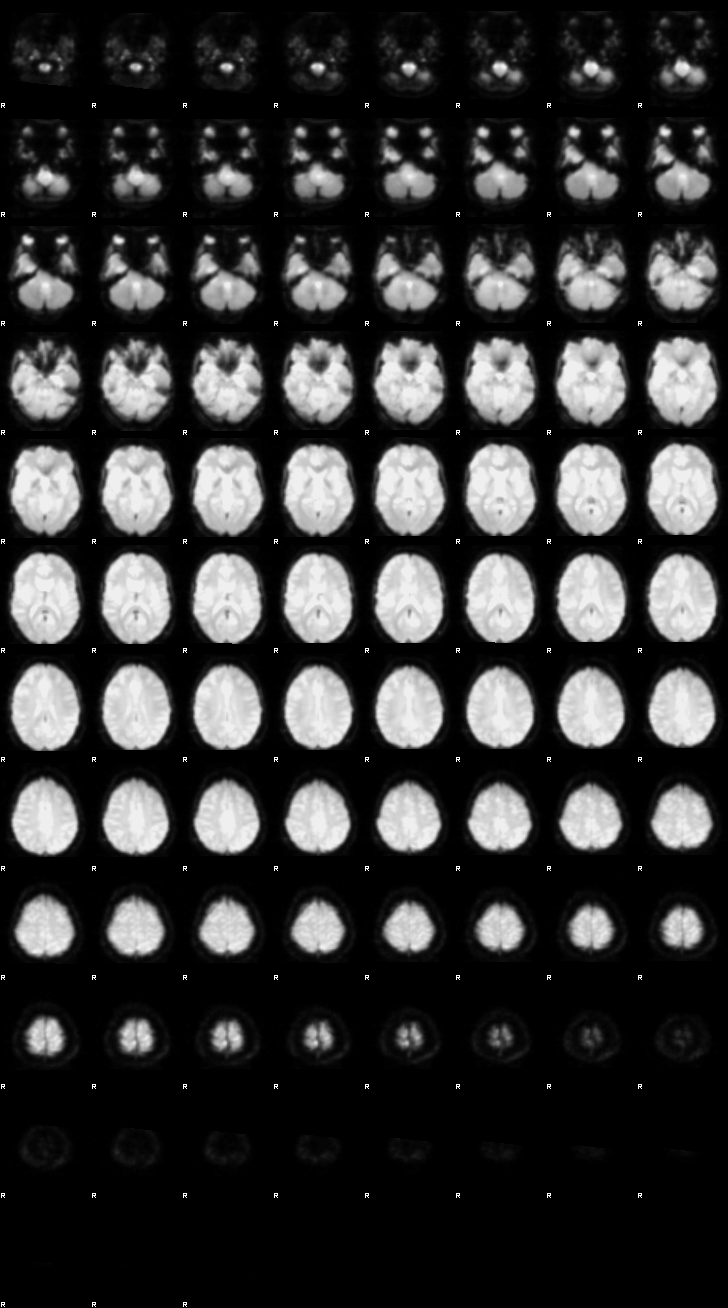

# functional image run 1, first volume

nv.load_volumes([{"path": "./FSL_preproc/sub-08_task-flanker_run-1_bold_vol0.nii.gz"}])

nv

Image(url='https://raw.githubusercontent.com/NeuroDesk/example-notebooks/refs/heads/main/books/images/fsl_preproc_run1.png')